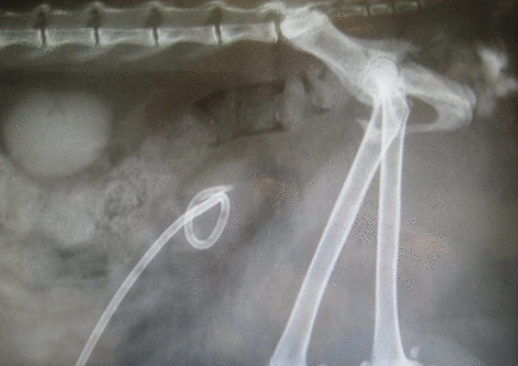

경피적 카테터라는건 소위 pigtail 카테터를 말한다.

이렇게 생긴 장비이고 요도폐색으로 초 응급상황인데 요도 카테터가 장착이 잘 되지 않거나

사고등의 손상으로 요도 확보가 되지 않는경우, 혹은 방광무력증 등에 의한 방광 기능장애시

요로 확보를 위해 사용될 수 있는 소모품이다.

장착을 완료하면

이렇게 장착되게 되고

이런식으로 피부를 통해 방광내 요를 뺄 수도 있다.